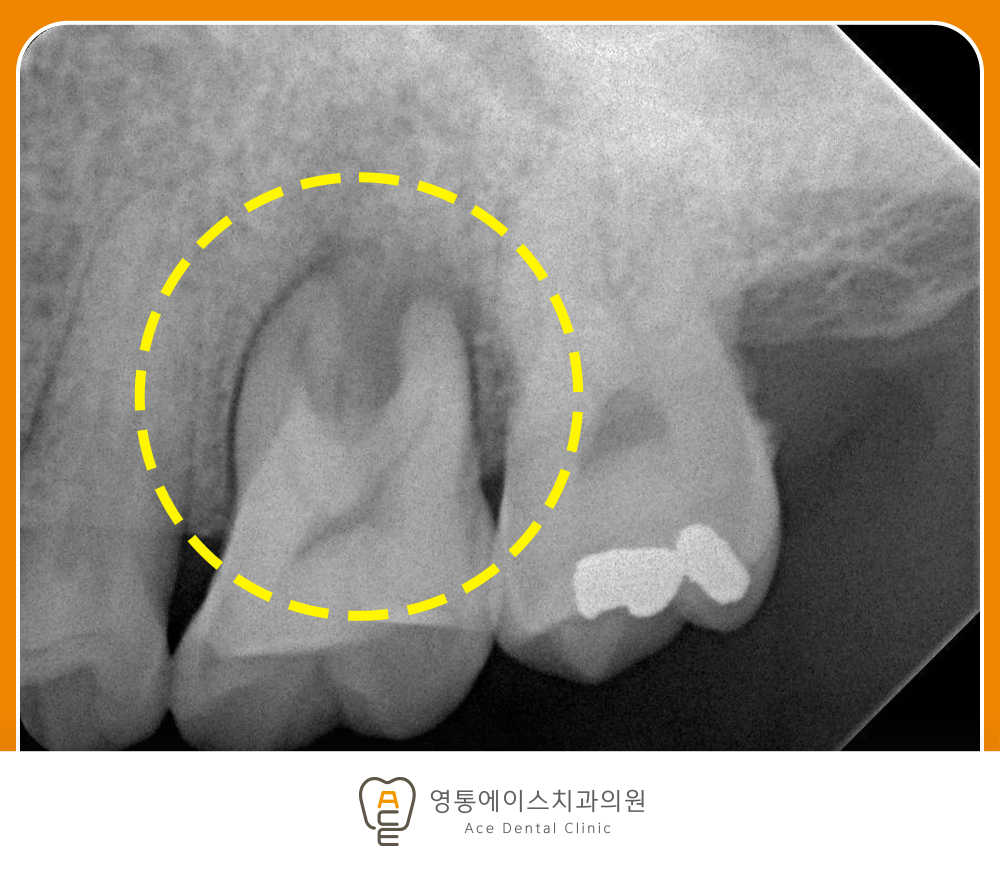

치료 전 사진/2025.08.20

잇몸질환은 초기에는 자각하기 어려운 것이 특징입니다. 양치할 때 피가 나는 정도로 시작되거나 잇몸이 약간 붓는 증상이 나타나지만, 통증이 크지 않아 대수롭지 않게 넘기는 경우가 많습니다. 하지만 이러한 상태를 방치하게 되면 염증이 점점 깊어지면서 잇몸뼈까지 손상될 수 있고, 결국 치아가 흔들리거나 빠지는 상황으로 이어질 수 있습니다.